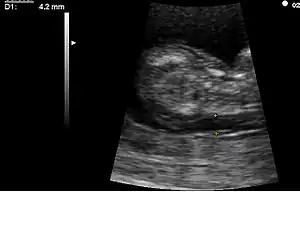

![]() Eco-Doppler demostrando insuficiencia mitral (incapacidad de la válvula para cerrarse completamente, provocando regurgitación de sangre hacia la aurícula izquierda, en azul. Esta patología valvular degenerativa puede aparecer precozmente en personas con SD. |